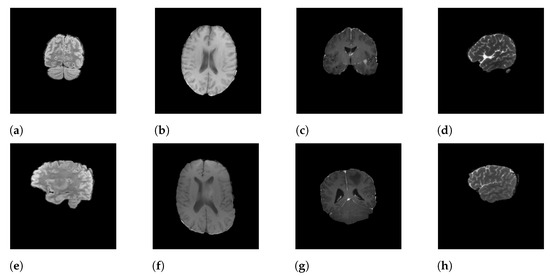

In this research, we focus on the RSNA-MICCAI dataset [9], a multi-center brain tumor MRI dataset that comes with two tasks; namely, tumor segmentation and MGMT detection. In this study, we only tackle the second one. In the dataset, each patient’s data is stored in a dedicated folder with a five-digit identification number. Each sample folder consists of four sub-folders corresponding to the four modalities of the MRI scans, including fluid attenuated inversion recovery (FLAIR), T1-weighted pre-contrast (T1w), T1-weighted post-contrast (T1Gd), and T2-weighted (T2), obtained from the video cut frames acquired by imaging. Each modality (i.e., scan type) specifies a focus during imaging. For instance, FLAIR captures the effect after cerebrospinal fluid (CSF) suppression, where liquid signals such as water are suppressed to highlight other parts. T2-weighted, on the other hand, highlights the difference in lateral tissue relaxation, and the combination of different effects provides a comprehensive description of the lesion from multiple perspectives. Each sample in the dataset is described by a quadruple of these four different imaging modalities. Figure 1 shows the four modalities of a positive sample (Figure 1a–d) and a negative sample (Figure 1e–h).

Figure 1.

Samples of MRI scans: (a–d) represent the FLAIR, T1w, T1Gd, and T2 modalities of a positive sample, and (e–h) represent the FLAIR, T1w, T1Gd, and T2 modalities of a negative sample.